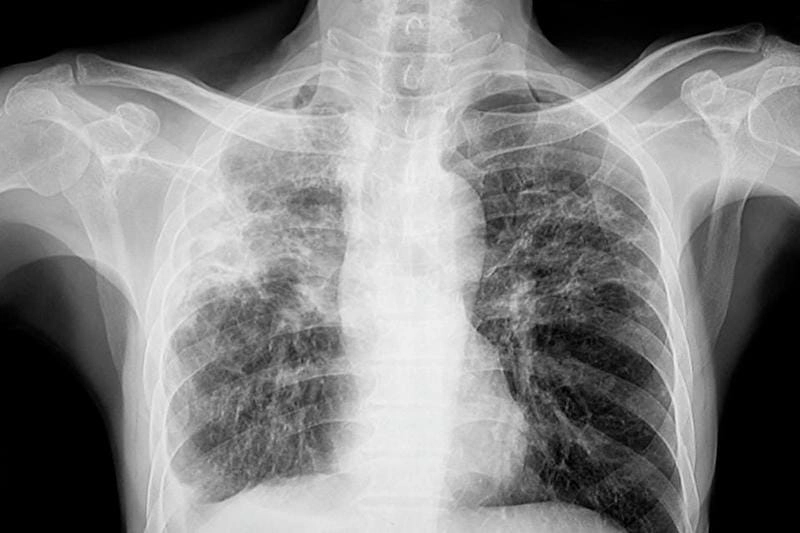

Bạn sẽ phải rùng mình khi chiêm ngưỡng hình ảnh bệnh lao phổi là như thế nào dưới ống kính y học thực tế. Những bức ảnh chụp X-quang cho thấy phổi bị tổn thương nặng, xuất hiện những đốm trắng mờ như bóng ma ám ảnh. Không chỉ là các tổn thương vật lý, đây còn là những “chứng tích sống” của căn bệnh âm thầm hủy hoại cơ thể qua từng hơi thở. Từ viêm nhẹ đến tổn thương lan rộng, hình ảnh bệnh lao phổi khiến người xem không thể rời mắt vì mức độ nghiêm trọng mà nó thể hiện rõ ràng qua từng chi tiết.

Cảnh báo: tổng hợp ảnh bệnh lao phổi chân thực này không dành cho người yếu tim. Đây là loạt hình ảnh y khoa được các chuyên gia sưu tầm và xác thực, ghi lại quá trình tiến triển của bệnh từ giai đoạn đầu đến giai đoạn nguy kịch. Từng mảng mô phổi bị ăn mòn, xơ hóa, hoại tử được phơi bày rõ nét dưới ánh sáng X-quang lạnh lùng. Những hình ảnh này không chỉ mang tính chất minh họa y học, mà còn là hồi chuông cảnh tỉnh cho bất kỳ ai còn lơ là với căn bệnh nguy hiểm này.